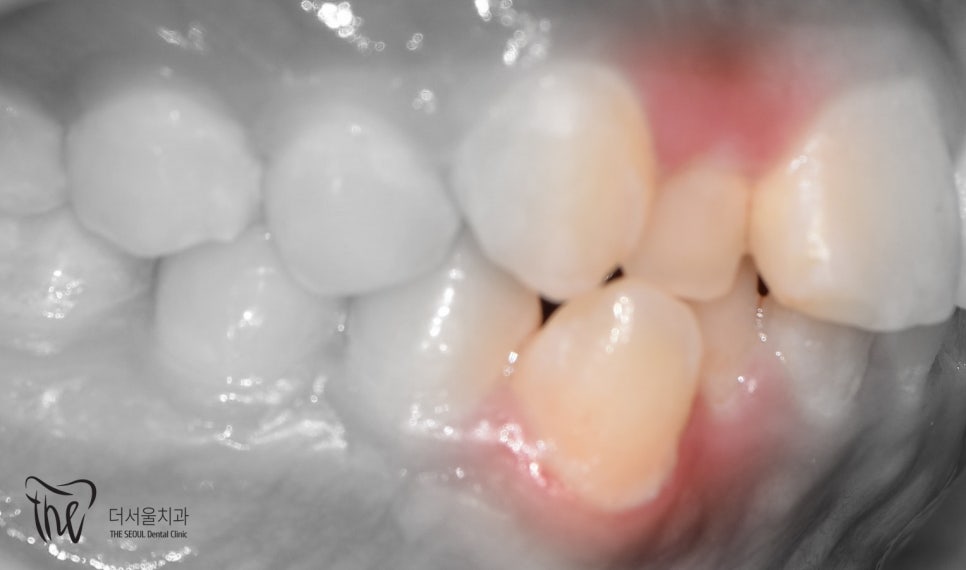

사진을 보면

*측절치에서 왜소치 가 관찰되고 있었으며

아랫니가 윗니를 덮고 있는 반대교합을 보였습니다.

측면에서 바라보면

송곳니가 튀어나온게 두드러졌으며

치열이 고르지 못하고

삐뚤빼뚤 한 것을 볼 수 있었습니다.